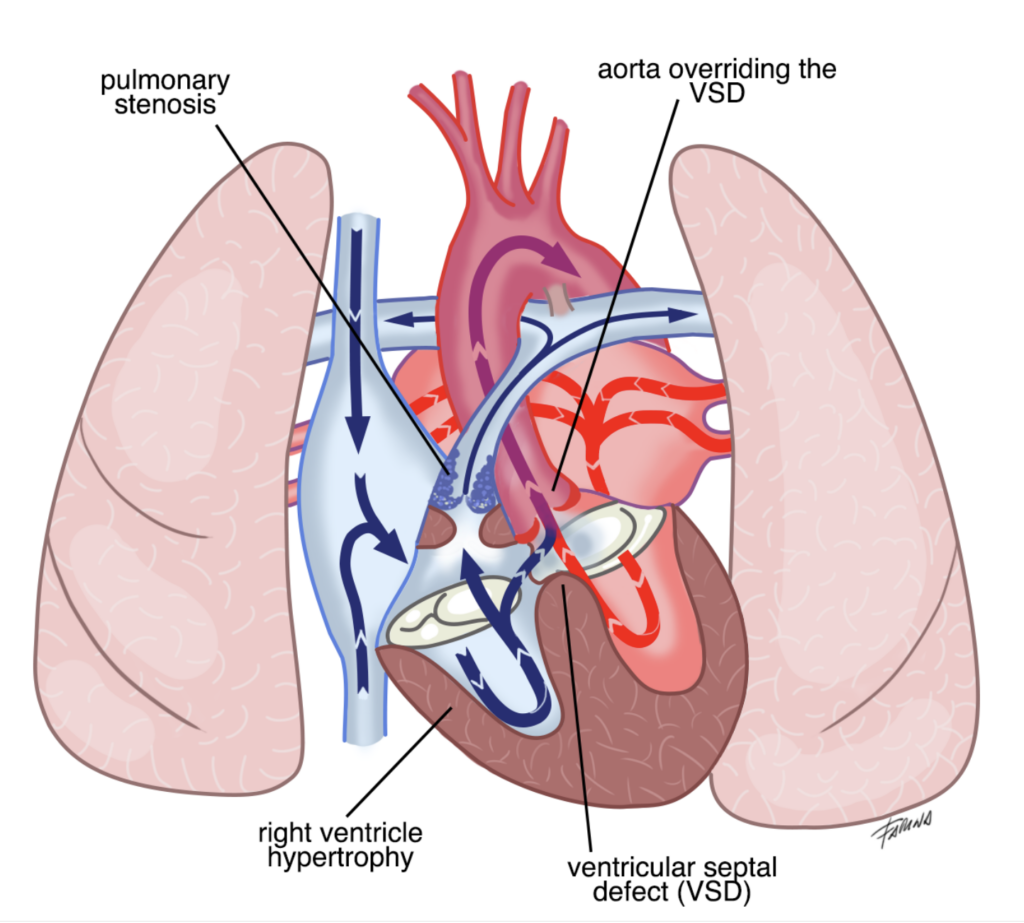

La tetralogia di Fallot è la più comune cardiopatia congenita in grado di causare cianosi, colorazione bluastra di cute e mucose. E’ caratterizzata da quattro componenti fondamentali, evidenziate nell’immagine: difetto interventricolare (una comunicazione anomala tra i due ventricoli), posizione dell’aorta a cavallo tra i due ventricoli e immediatamente sopra il difetto, restringimento della valvola polmonare e del tratto muscolare al di sotto di essa e ipertrofia (irrobustimento) del ventricolo destro.

Durante la contrazione dei ventricoli, il sangue in ventricolo destro (venoso e povero in ossigeno) ha a disposizione una strada a minor resistenza rispetto a quella fisiologica: può infatti passare attraverso il difetto interventricolare ed essere eiettato dal ventricolo sinistro in aorta. Di conseguenza, la concentrazione di ossigeno nel sangue arterioso risulterà ridotta in modo proporzionale alla gravità della patologia e/o in relazione a fenomeni transitori di aumento delle resistenze polmonari (pianto, stress, sforzo fisico, defecazione, febbre). L’eccesso di emoglobina deossigenata causa la colorazione bluastra di cute e mucose (cianosi). Da qui il nome di “sindrome del bambino blu”.